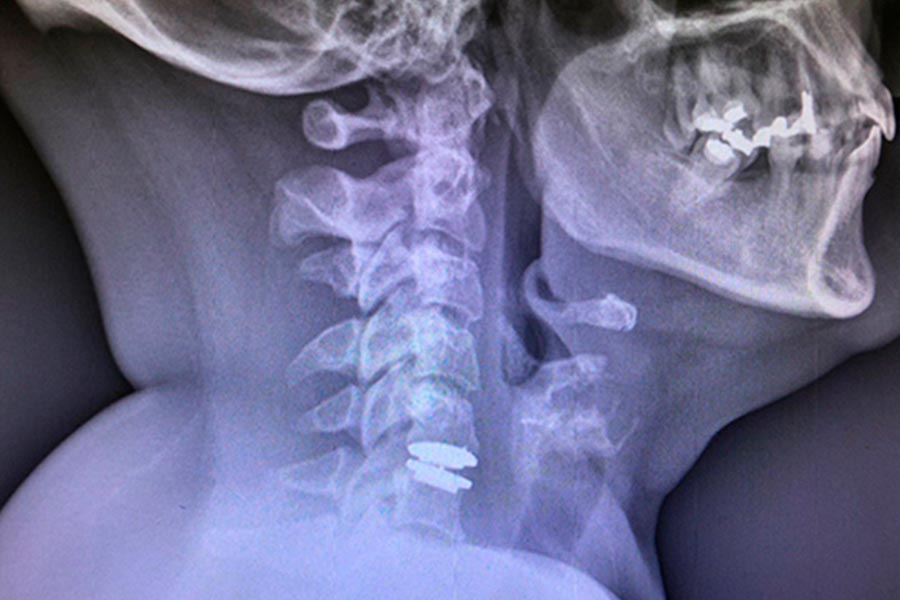

En este caso clínico, los especialistas del Instituto de Cirugía Avanzada de Columna intervienen a una paciente joven mediante artrodesis cervical.

Tras hallar una hernia discal con estrechamiento del foramen se decide abordar la lesión con una técnica mínimamente invasiva de Artroplastia.

En este caso, la paciente ya ha sido intervenida de disco cervical, sin haber realizado una liberación posterior. Se realiza un recambio de disco.

Es un caso de cirugía cervical de una paciente de mediana edad que fue operada hace aproximadamente 6 años.

La paciente presenta varias hernias discales cervicales, empeoradas por la presencia de artrosis en la zona y que provoca dolencias en el lado derecho (brazos y cuello).

El paciente acude a la consulta tras sufrir fuertes dolores en la zona, provocados por una artrodesis no efectiva. Implante de prótesis cervical.

En este caso clínico nos encontramos ante una paciente que acude a nuestra consulta por un dolor agudo en el brazo izquierdo y un tinel muy positivo.

Caso de extrema dificultad en el que podemos ver a un paciente con dolor crónico cervical, parentesias MMSS y hormigueo en los miembros superiores.

Nos encontramos ante un paciente con dolor agudo que presenta tres hernias discales cervicales. Su situación no mejoraba con medicación ni tratamiento.